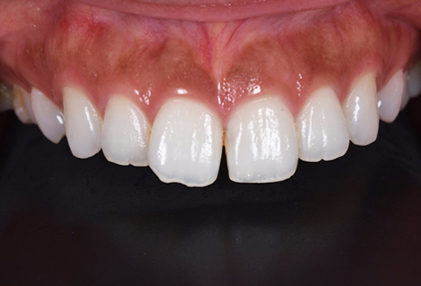

仮歯

セラミックの前に仮歯を調整している段階になります。できればということで歯の長さも短くしたいというリクエストがありましたので、仮歯で調整をしながら様子を見ました。

歯の長さを短くする際に歯を削りますので神経の治療が必要になることがありますので、しみたり・噛んで痛くないか?を約1ヶ月様子を見ました。色・形など仮歯でほぼ問題ないということでしたので、最終的な型採りをしました。

セラミックセット

最終的なジルコニアボンドクラウンをセットしました。すきっ歯がまずなくなりました。また、長かった歯が短くなりましたので本人の希望に沿うことができました。